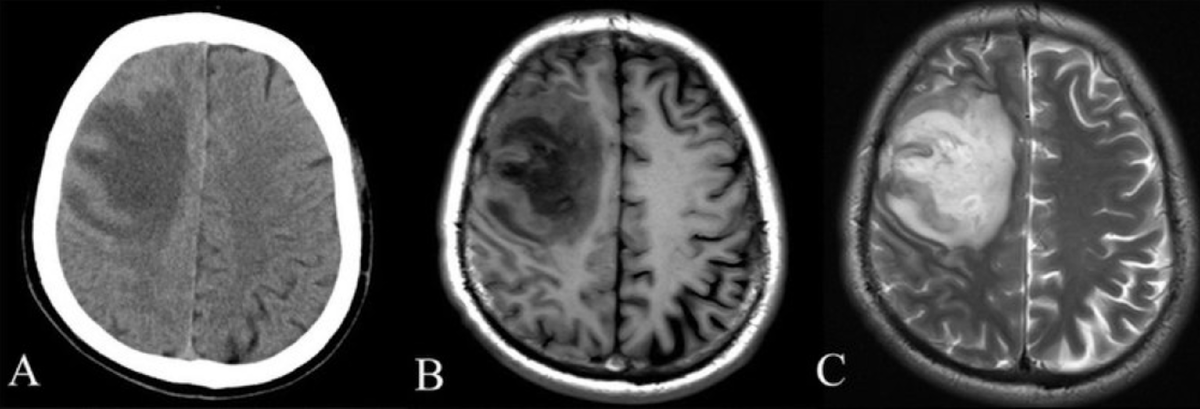

Любые очаговые изменения в паренхиме мозга, кроме острого кровоизлияния (опухоли, демиелинизация, энцефалит). На КТ их часто просто не видно. В заключении КТ может стоять «норма» и будет упущено драгоценное время.

Патология гипофиза, мостомозжечковых углов, ствола мозга, черепно-мозговых нервов. КТ здесь просто «слепа».